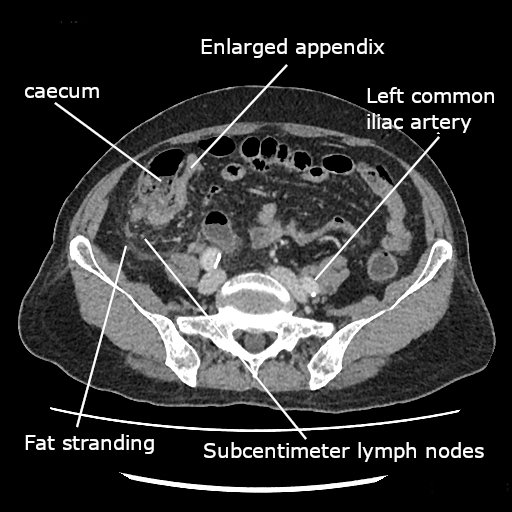

Dilated appendix (12mm), appendicolith, periappendiceal fat stranding, RLQ free fluid